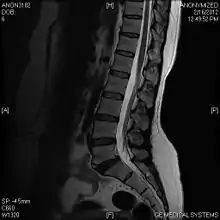

T2 W Sagittal image

Limbus Vertebra L5